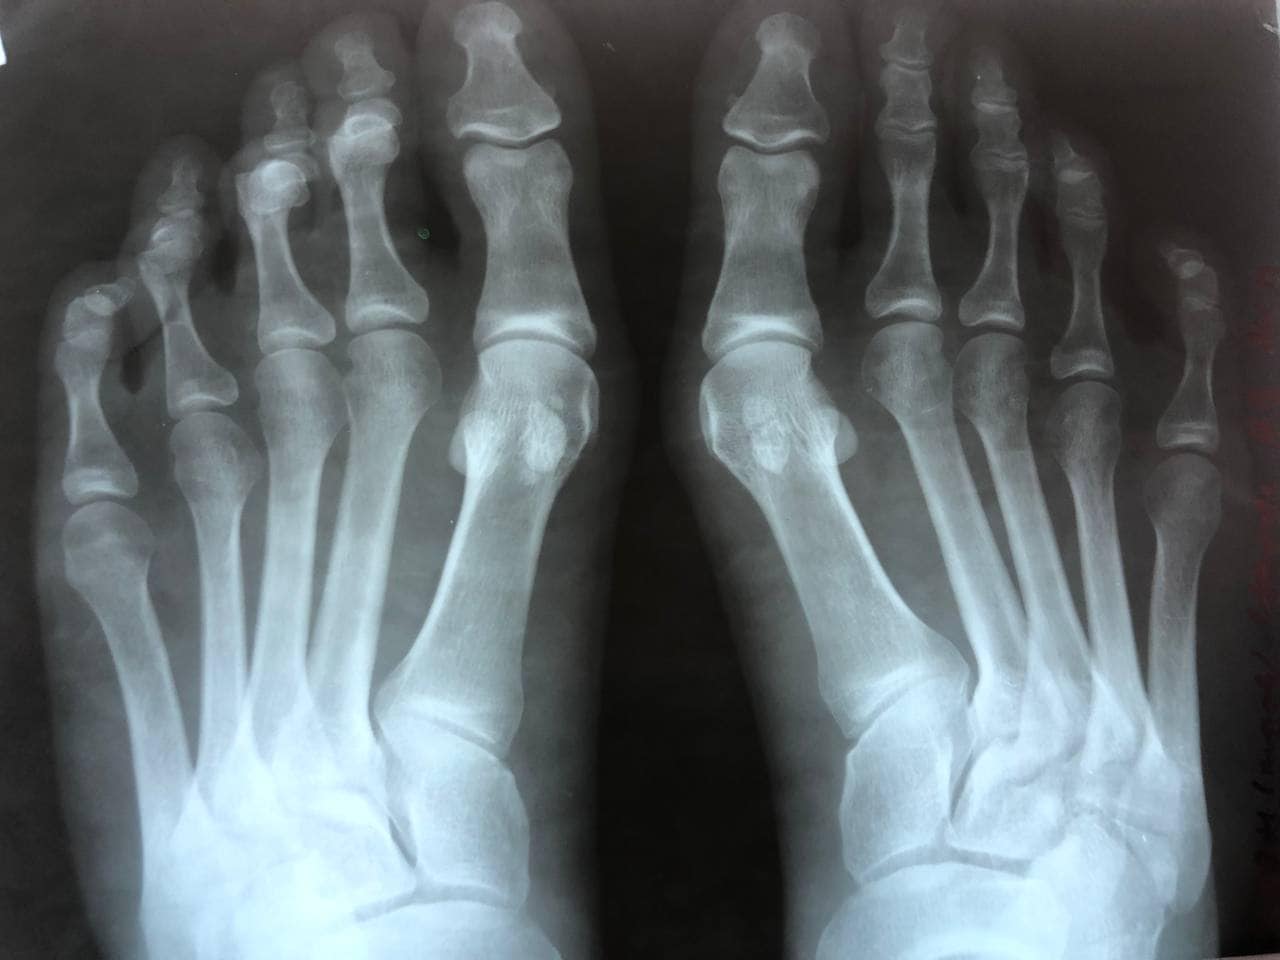

24-річна пацієнтка КНП «НЦМЛ» відчувала дискомфорт при ходьбі за рахунок викривлення перших пальців обох стоп, повідомляють у фейсбуці установи.

У неділю, 26 вересня, хворій під спинальною анестезією провели корегуючу операцію та реліз сухожилок першого пальця обох стоп.

Операція проведена успішно. Пацієнтці дали дозвіл вже з наступного дня навантажувати ногу.